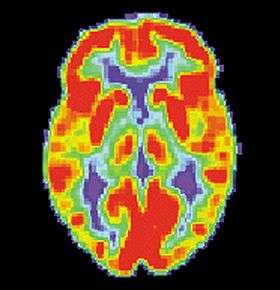

PET scan of a healthy brain - Image courtesy of US National Institute on Aging Alzheimer's Disease Education and Referral Center